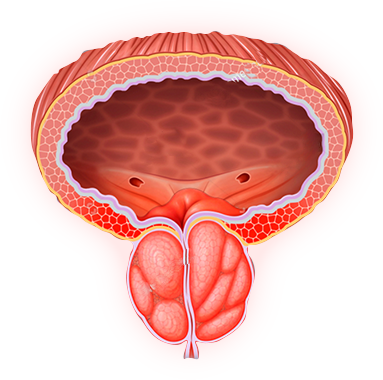

El Beta-Sitosterol es un fitoesterol estructuralmente similar al colesterol pero con efectos opuestos: inhibe competitivamente la enzima 5-alfa-reductasa y modula la respuesta de factores de crecimiento en la próstata. Su acción específica en HPB es reducir el residuo vesical postmiccional — el volumen de orina que queda en la vejiga tras orinar, responsable de infecciones recurrentes y urgencia. Meta-análisis documentan mejora del flujo urinario máximo en 3,9 mL/s.

✦ Inhibe 5-alfa-reductasa✦ +3,9 mL/s flujo✦ -28,6 mL residuo